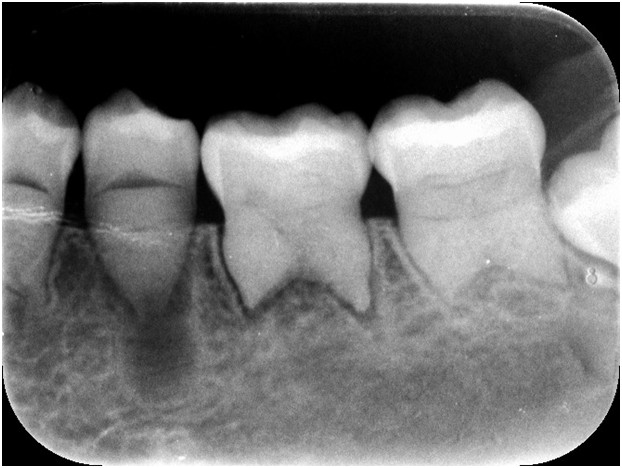

Do gabinetu zgłasza się 20-letnia pacjentka z bólem zęba 35. Ząb jest bolesny na nagryzanie, nie reaguje na bodźce termiczne. Brak widocznego nacieku zapalnego, brak widocznych ognisk próchnicy, ruchomość zęba II°. Reakcja na chlorek etylu ujemna. Obraz radiologiczny w załączeniu. Na podstawie opisanych objawów oraz zdjęcia RTG wskaż prawidłowe postępowanie oraz rokowanie: